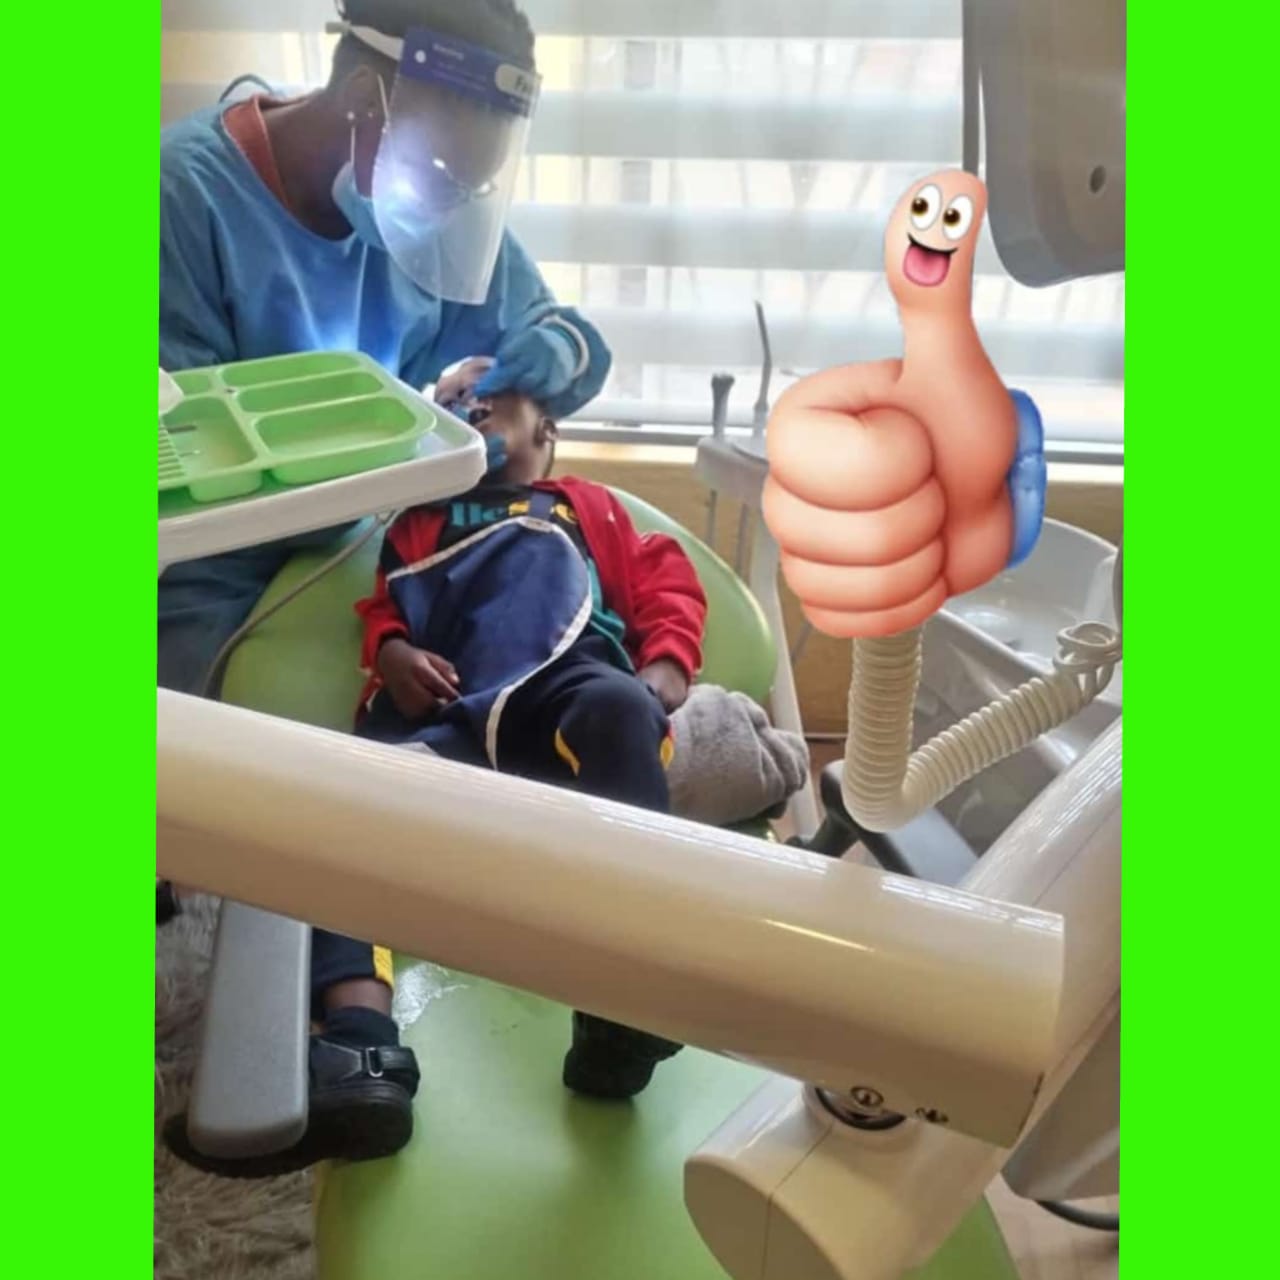

- Paediatric Theatre

Our Latest Work